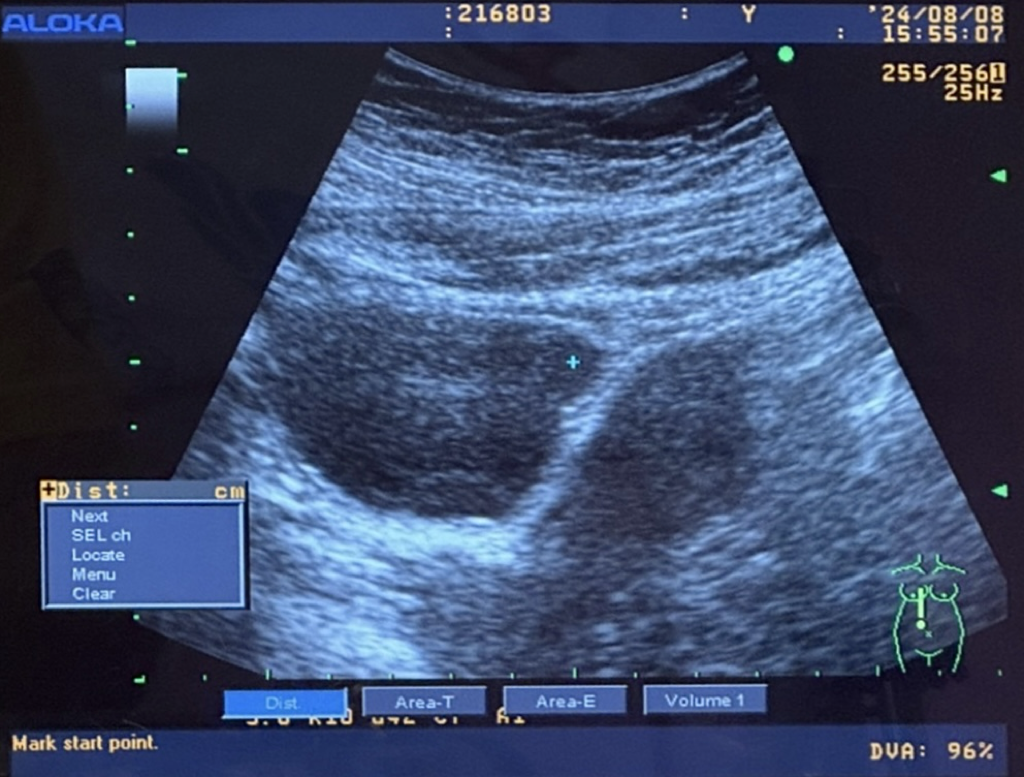

哪一個才是胎囊跟胚胎啊